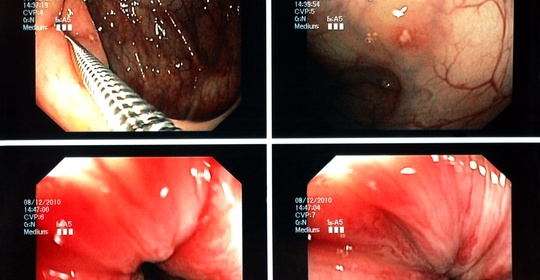

硬腦膜膿腫:診斷與治療方法

硬腦膜膿腫:頸椎硬膜外膿瘍與脊髓椎管炎的鑑別與治療

本文介紹了兩種與頸椎相關的疾病——頸椎硬膜外膿瘍和脊髓椎管炎。前者是一種嚴重的感染性疾病,需緊急處理以防止神經系統併發症;後者則需要及時治療以控制病情進展。對於這兩種疾病,應儘快就醫並遵循專業醫生的指導進行治療。

硬腦膜膿腫:病因、症狀及治療方法